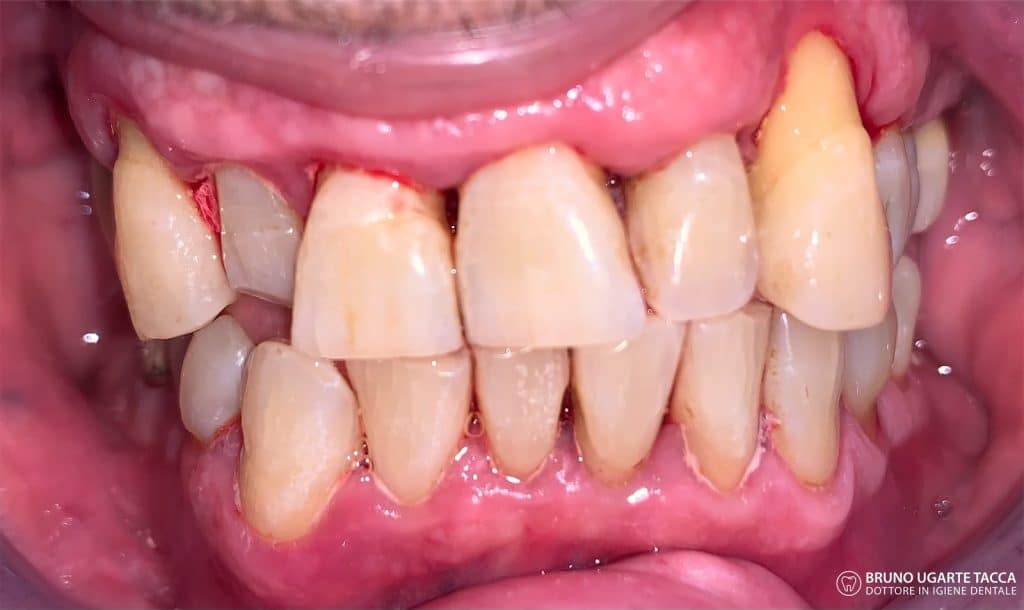

The patient is also instructed to rinse her mouth and spray her tonsils with one

0.2% CHX solution twice a day for a period of 2 months after.

(Quirynen et al. 1995, Mongardini et al. 1999)